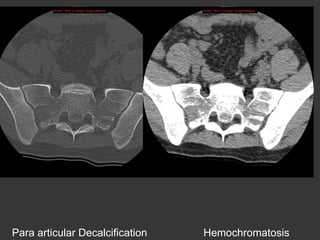

Para articular bone

Para articular Decalcification

Hemochromatosis

Inflam. Rh.

<45 years

HyperParaTh

Kidney insufficiency

Sacro-iliac(s)?

Infectious

Osteoarthritis

Teenager:

Pseudo-enlargment

< 20 years

>45 years